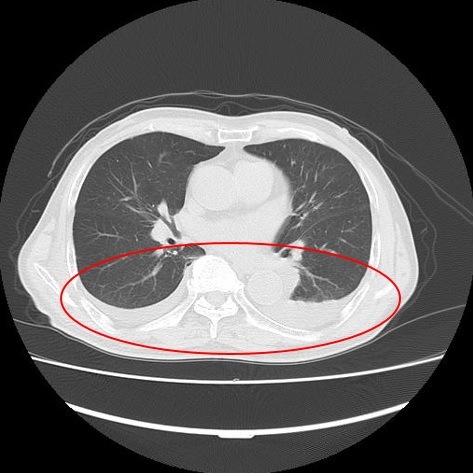

▼CT検査で得られる画像

例2 胸水